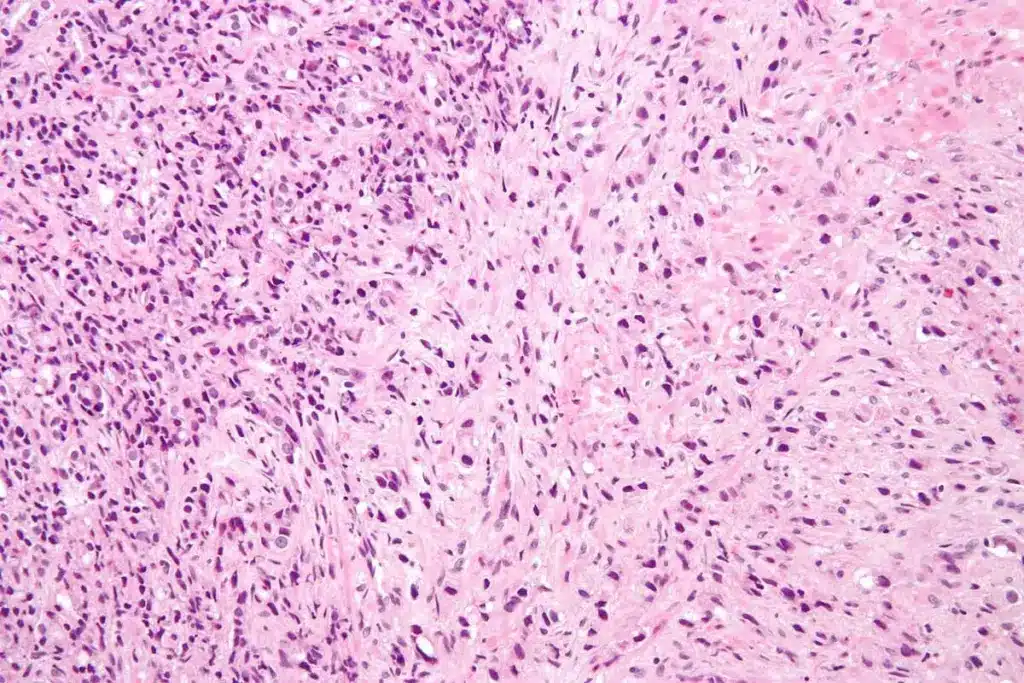

This test takes tissue from the prostate gland for a microscope check. It looks for abnormal cell growth or cancer. A urologist usually does this.

A prostate biopsy is a medical test that takes small tissue samples from the prostate gland. It’s key for finding prostate cancer and other issues.